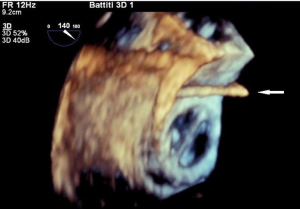

Both transthoracic echocardiography (TTE) and transoesophageal echocardiography (TEE) are the main imaging modalities for diagnosis of IE The European Society of Cardiology (ESC) classify echocardiography as 1B recommendation with echocardiographic results an important Duke criterion (2). Diagnosis based on echocardiographic images has high sensitivity and specificity to detect vegetations, a distinctive sign of IE, particularly if it measures >5 mm (Table 1) and for valve detachment (3). It is however less accurate when it comes to detecting abscesses, aneurysms, pseudoaneurysms, and fistulas. Echocardiography allows the rapid detection of vegetations (Figures 1,2), by measuring the major and minor axes of these, in addition to allowing differentiation from other intracardiac masses, informing the operator on location, mobility (fixed, mobile, oscillating) (Figure 3), echogenicity and potential complications such as the presence of leaks, fistulas, and dehiscences (2,4).

In a study of suspected right-sided endocarditis, TTE performed as well as TEE in the detection of vegetations (22). RT3D TEE also has a role in patients with tricuspid valve IE as it allows enhanced visualization of the tricuspid valve apparatus, vegetations, and surrounding structures compared to 2D TEE (23). In patients with a tricuspid ring or tricuspid valve prosthesis and/or electrophysiological devices, RT3D echocardiography can detect vegetations and their exact origins, permitting real-time therapeutic interventions or device extraction (Figure 5).